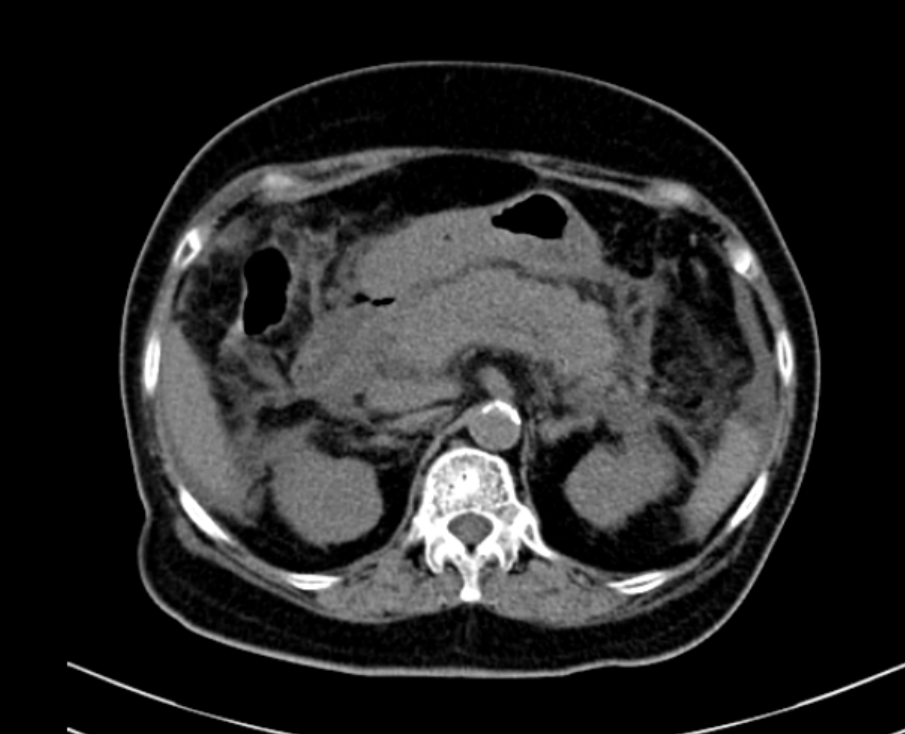

- CT scanner, MRI tụy: Đây là 2 phương pháp có giá trị chính xác trong chẩn đoán cũng như trong tiên lượng bệnh, cho biết rõ hình ảnh, kích thước, mức độ tổn thương ở tụy, quanh tụy, trong ổ bụng.

Hình ảnh CT scanner 1 ca viêm tụy cấp

Siêu âm bụng, CT ổ bụng: Tụy kích thước lớn, phù nề

Hình ảnh CT: Tụy phù nề